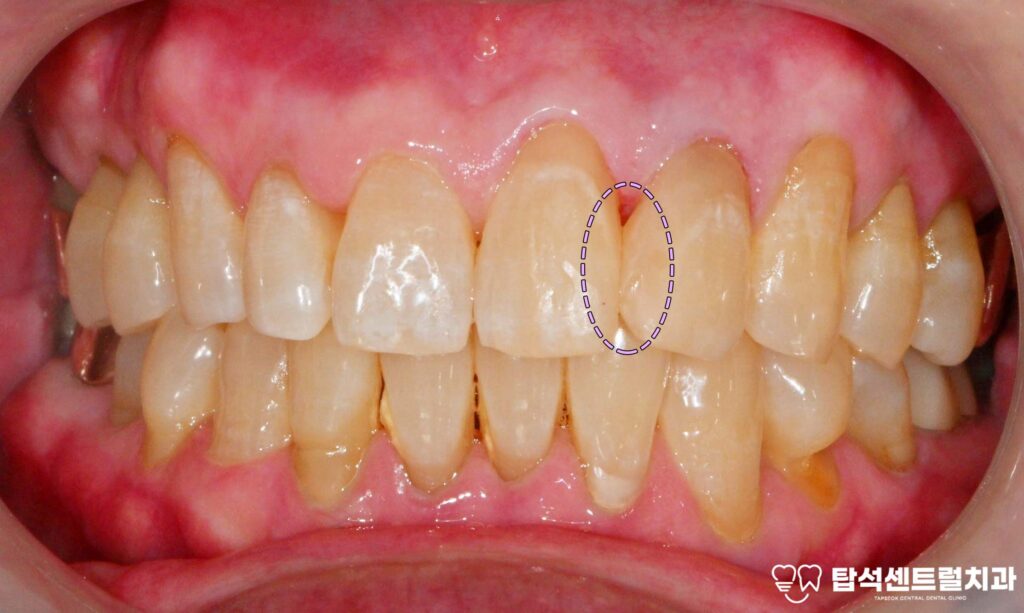

벌어진 앞니 사이 공간, 어떻게 개선할 수 있을까

벌어진 앞니 사이에 공간이 있으면

벌어진 공간 사이로 음식물이 끼면

잇몸에 자극을 주어

염증이 발생하는 상황도

생각해볼 수 있습니다.

벌어진 앞니 부위 결과와 관리 방법 소개

벌어진 윗니 사이 부분을 메운 후에는

자연스러운 형태로

회복되는 것을 확인할 수 있습니다.